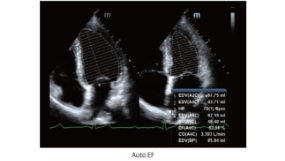

EF Otomatis

EF Otomatis merupakan cara cerdas untuk menganalisis klip gema 2D untuk mengenali bingkai diastol & sistol dan menghasilkan serangkaian pengukuran untuk mengevaluasi fungsi ventrikel kiri untuk meningkatkan produktivitas, seperti EDV/ESV/EF.